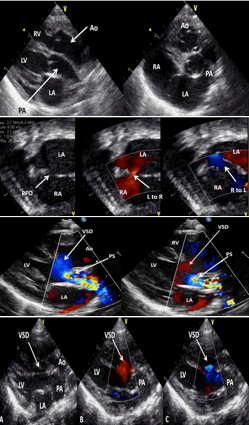

Pre-op Echo Findings of D-TGA

PLAX visualization of side-by-side/parallel course of AO & PA

AO will be anterior to PA

PSAX visualization of both semilunar valves in short axis with AO anterior

Establish patency of PDA, ASD/PFO or presence of VSD

Verify coronary anatomy (important for one of the repair options

What are these images of?

D-TGA